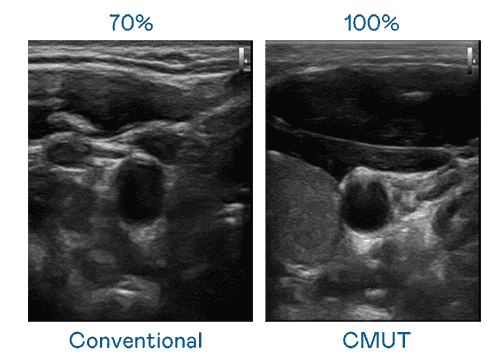

CMUT 技术是一种用电容式微机电元件来产生超音波讯号的技术。。。。与传统 PZT 压电式技术相比,,,CMUT 频宽增加 30%,,,更宽频的超音波讯号让影像解析度大幅提升,,,是实现高影像品质医疗超音波扫描、、、促进精准医疗发展的关键技术。。。。

大频宽带来超清晰影像

超音波影像的解析度高低,,,,首先取决于探头能发出的讯号频宽。。彩霸王 CMUT 可提供高清晰的超音波讯号,,,,提供高频宽、、高灵敏度、、、影像纹理细节更高的超音波影像,,,协助医护人员缩短影像判读时间及利用精准的医疗影像进行诊断。。。